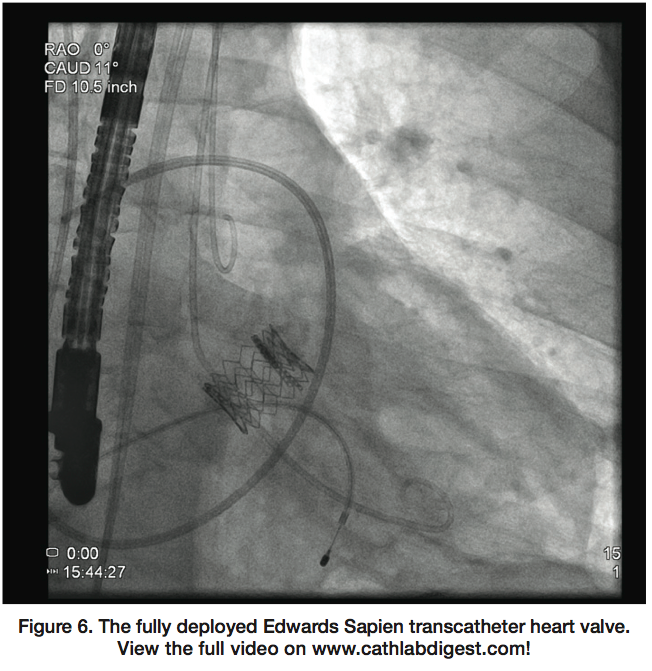

General endotracheal anesthesia was utilized, as was intra-procedural transesophageal echocardiography (TEE). The procedure was performed completely percutaneously, without the need for surgical vascular access. The native aortic valve was crossed, and the Edwards Sapien valve was deployed with rapid pacing after careful positioning under fluoroscopic and TEE guidance (Figure 6; video available at www.cathlabdigest.com). Following deployment of the valve, TEE demonstrated a well-positioned valve with trivial central aortic regurgitation and no paravalvular regurgitation. Clinically, the patient tolerated the procedure very well and was extubated without difficulty at the conclusion of the procedure while still in the hybrid catheterization laboratory.